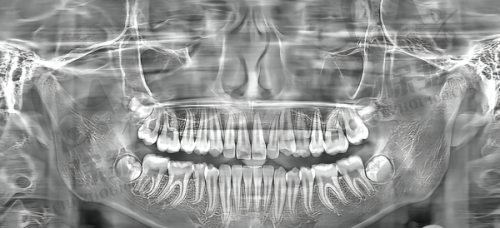

普宁金铂利口腔采用了全数字化的齿科设施和设备,拥有智能化口腔CT、全景X光机、CBCT机、高频电刀、根管填充器、iTero口内扫描仪等正规精良设备。这些设备能够为患者提供精细、有效的诊疗体验,帮助医生更正确地诊断病情,制定合适的治疗方案。